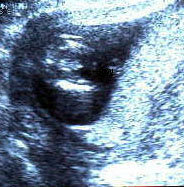

الأسبوع ال17